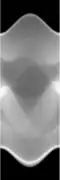

Concretely, for the two-dimensional Radon transform, the dual transform is given by: In the context of image processing, the dual transform is commonly called back-projection[4] as it takes a function defined on each line in the plane and 'smears' or projects it back over the line to produce an image.

The process of reconstruction produces the image (or function in the previous section) from its projection data. Reconstruction is an inverse problem.

Compared with the Filtered Back-projection method, iterative reconstruction costs large computation time, limiting its practical use. However, due to the ill-posedness of Radon Inversion, the Filtered Back-projection method may be infeasible in the presence of discontinuity or noise. Iterative reconstruction methods (e.g. iterative Sparse Asymptotic Minimum Variance[10]) could provide metal artefact reduction, noise and dose reduction for the reconstructed result that attract much research interest around the world.